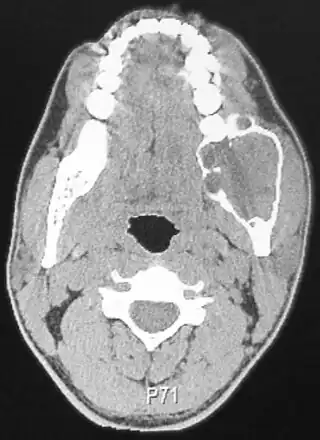

![]() Una Tomografía de un paciente afectado por un ameloblastoma | ||

El ameloblastoma se sospecha por los síntomas y estudios de imagen como radiografías, el diagnóstico de certeza precisa una biopsia y estudio histológico. Radiográficamente, aparece como una zona radiolúcida en el hueso, de tamaño y apariencia variables, en ocasiones es una lesión única, bien demarcada, otras veces se presenta como una «pompa de jabón» multiloculada. La reabsorción de las raíces de los dientes involucrados puede observarse en algunos casos, pero no es exclusiva del ameloblastoma. La enfermedad afecta con más frecuencia al cuerpo posterior y el ángulo de la mandíbula, pero puede presentarse en cualquier parte del maxilar inferior o superior. El ameloblastoma se asocia a menudo con muelas del juicio impactadas, una de las razones para que los odontólogos recomienden su extracción.